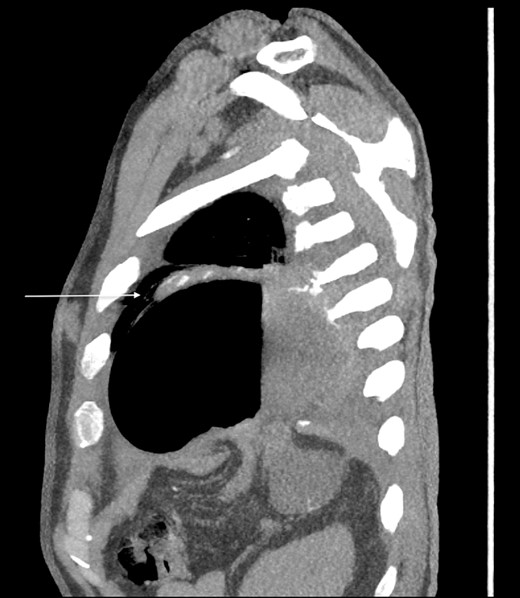

Thirty-seven days after the initial visit, the patient returned to the emergency department with burning epigastric pain that radiated to the left upper chest and hematemesis. Vital signs revealed tachycardia and hypertension. A comprehensive physical exam was significant for decreased breath sounds at the left base and tenderness in the left upper quadrant without signs of peritonitis. Pertinent laboratory findings showed leukocytosis with a left shift and thrombocytosis. A chest X-ray showed a significant portion of the gastric body in the left hemithorax (Fig. 1). A pulmonary CT angiogram found segmental and subsegmental pulmonary emboli in both lungs with no evidence of right heart strain and a left pleural effusion. A left diaphragmatic hernia with the “dangling diaphragm” sign can be seen on the sagittal view (Fig. 2). The coronal view shows discontinuity of the diaphragm and the “collar” sign (Fig. 3); the axial view shows the “dependent viscera” sign and thoracic fluid abutting abdominal viscera (Fig. 4).

Sagittal CT showing gastric body herniating through diaphragmatic defect and the “dangling diaphragm” sign (arrow).